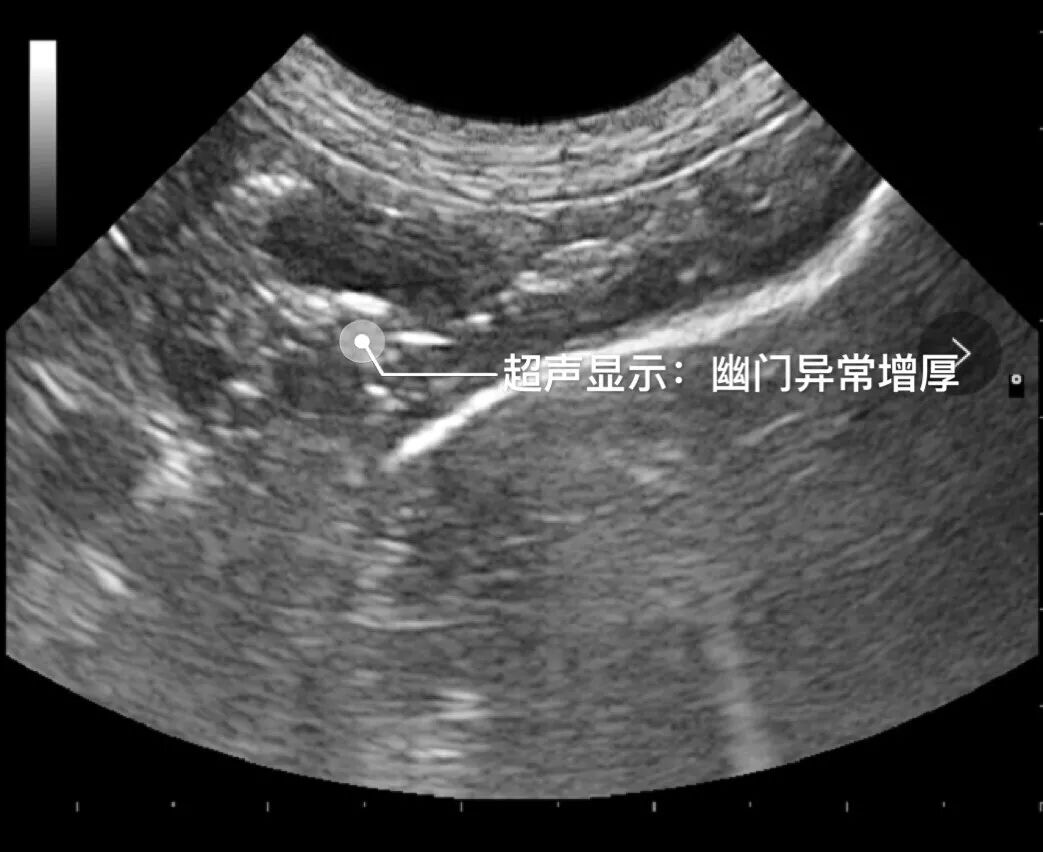

DR及B超检查结果显示:阿呆胃扩张,内部有大量积液,以及十二指肠部位有肿块,医生初步诊断为堵塞性呕吐。

▲超声显示-幽门异常增厚

为了进一步确诊,医生决定对阿呆进行开腹探查手术。